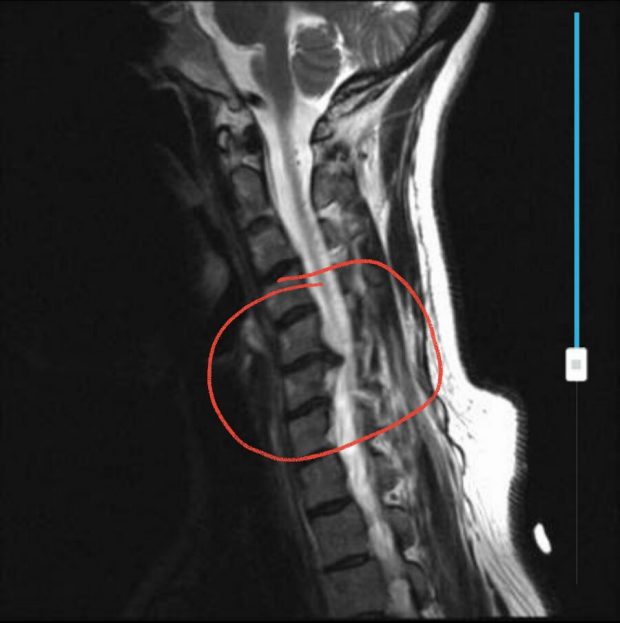

He ordered an MRI straightaway just to rule out anything serious in the nerves. And there it was, a very obvious slipped disc at C6. That’s upper neck, not the usual lower back position. And we found out there’s a weakness in my left arm, caused by the nerve compression.